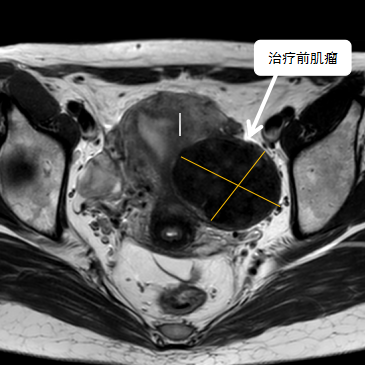

術(shù)前影像資料

經(jīng)過兩個月的藥物預(yù)處理,完善術(shù)前準(zhǔn)備,治療當(dāng)天陳主任帶領(lǐng)團隊在3.0T磁共振清晰圖像引導(dǎo)下對子宮肌瘤進行精準(zhǔn)消融,患者全程清醒,沒有明顯疼痛,經(jīng)過1個多小時的精細操作,手術(shù)非常成功,消融率接近90%,內(nèi)膜未見損傷!觀察一個小時后患者即自行回家。

術(shù)后即刻行增強磁共振檢查,顯示病變被消融近90%,內(nèi)膜未見損傷